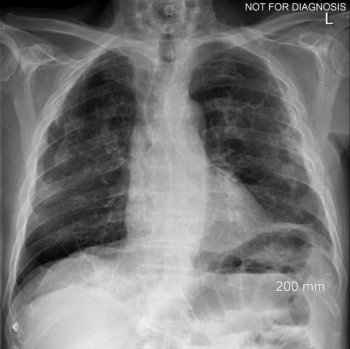

Can you diagnose this patient with a deformed chest wall and chronic history of gradual shortness of breath?